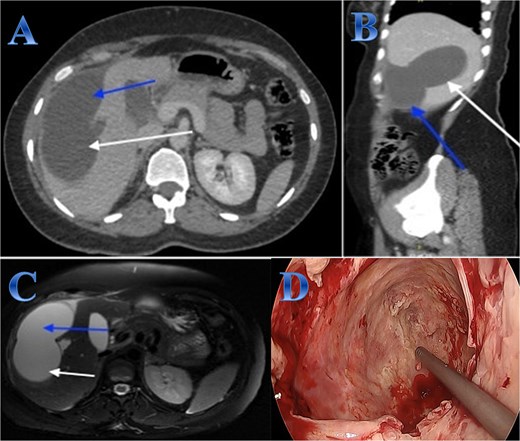

A 35-year-old lady with developed right upper quadrant abdominal pain suddenly. The laboratory tests showed a mild elevation of white blood cells and bilirubin levels. Abdominal US revealed a cystic structure extending from the right to the left hepatic lobes measuring 14 × 5 cm. CT with contrast revealed right hepatic intra-parenchymal cystic lesion with sub-capsular extension (Fig. 2).

Case 2. (A & B) Sagittal and axial CT cuts of the abdomen at venous phase showing right hepatic intra-parenchymal cystic lesion with subcapsular extension with no obvious post contrast enhancement. (C) MRI images showing right hepatic intra-parenchymal cystic lesion with subcapsular extension, proven to be sealed perforation. (D) The intraoperative finding after laparoscopic endocystectomy and the area of the cyst which was occupying the right hemi-liver under the ribs and reaching the diaphragm.

Laparoscopic endocystectomy was recommended. The liver was explored, and the cyst was isolated using gauze soaked in hypertonic saline. A suction device was used to puncture the cyst and aspirate the cyst fluid. Hypertonic saline was injected into the cyst (Fig. 2).